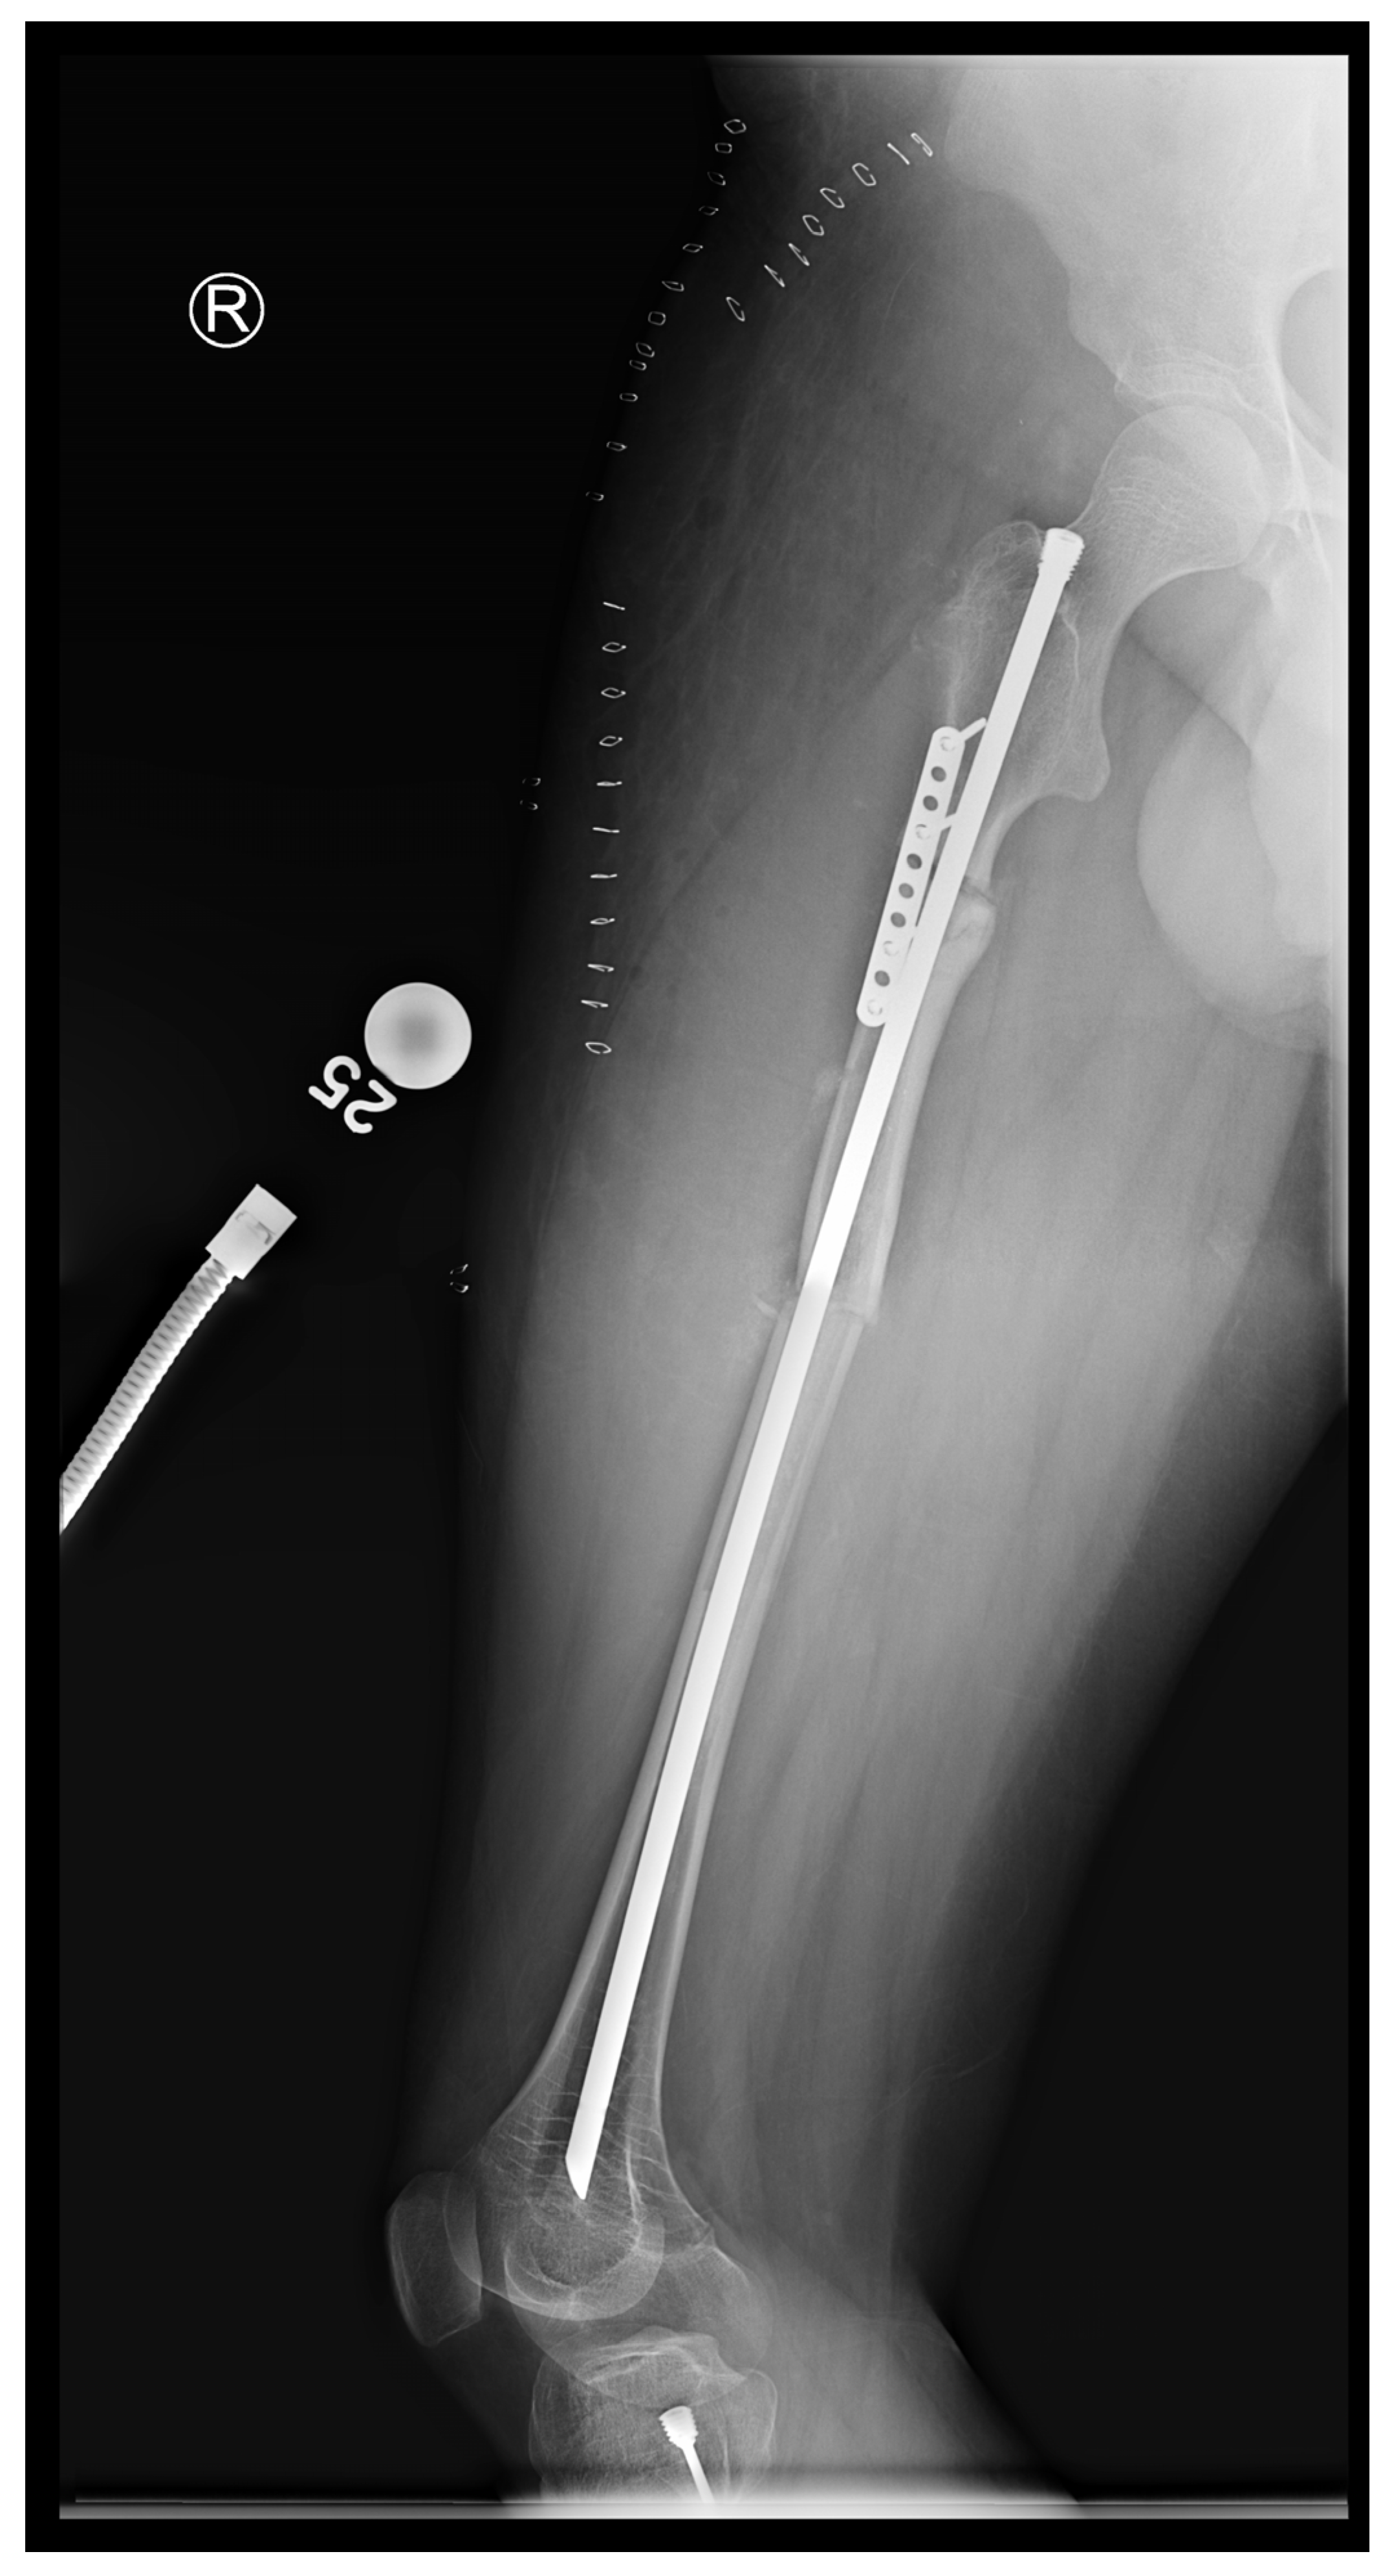

In the third case, a 16-year-old skeletally mature patient with OI was scheduled to undergo revision from FD rod to SLIM nail after presenting with pain due to stress fractures and wild deformity in his proximal right femur (Figure 11). The FD rod was removed, and then, using a piriformis entry point, access to the femur and proximal reaming was performed. There were two CORAs; the first CORA was identified in the subtrochanteric region, and a percutaneous osteotomy technique was performed to realign the bone, and then reaming was continued (Figure 12). The second CORA was identified, and another percutaneous osteotomy was performed, and the bone was cracked with a closed osteoclasis technique, and then reaming was continued in the distal segment (Figure 13). The SLIM nail was then inserted and had an excellent fit. The subtrochanteric region was under high stress, so a 2.7 Smith and Nephew EVOS plate to further stabilize the segment and control the rotation. Two screws were placed above and below (Figure 14). In this case, the indication for the use of the SLIM nail was the need to revise the existing telescoping FD rod in a skeletally mature patient to a solid nail. As the intramedullary canal was too small to accommodate a larger solid nail, a SLIM nail was used instead. The use of a plate as an adjunct to an intramedullary nail is also shown.

Figure 11.

Pre-operative X-ray showing right femur stress fracture.

Figure 14.

Post-operative X-ray showing SLIM nail and plate.